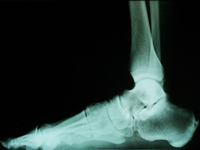

JUANETE

Prominencia en la articulación del dedo gordo. Puede desviar a dedos pequeños.

Tratamiento

En Clínica Aivar, con 24 años de experiencia, aconsejamos operar cuanto antes, por dolor o por afectar a otros dedos.

Cuanto menor es la deformidad, la técnica es menos agresiva y mejores los resultados.

Operamos con anestesia local. el paciente sale caminando con calzado postquirurgico, que mantendrá 10-15 días.